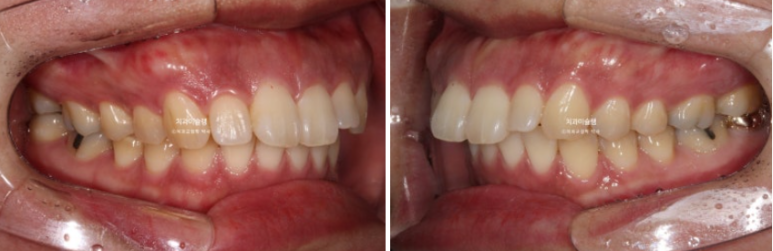

This patient was referred to us for orthodontic treatment three years ago.

You can see midline discrepancy and deep overbite.

The upper front teeth protrude forward.

According to the skeletal analysis, the patient has a recessed chin, meaning the lower jaw is smaller than the upper jaw.

The treatment plan was to extract only two upper premolars and use the wisdom tooth space in the lower jaw to move the teeth backward without extraction.

The patient chose Clippy-C, and treatment began.